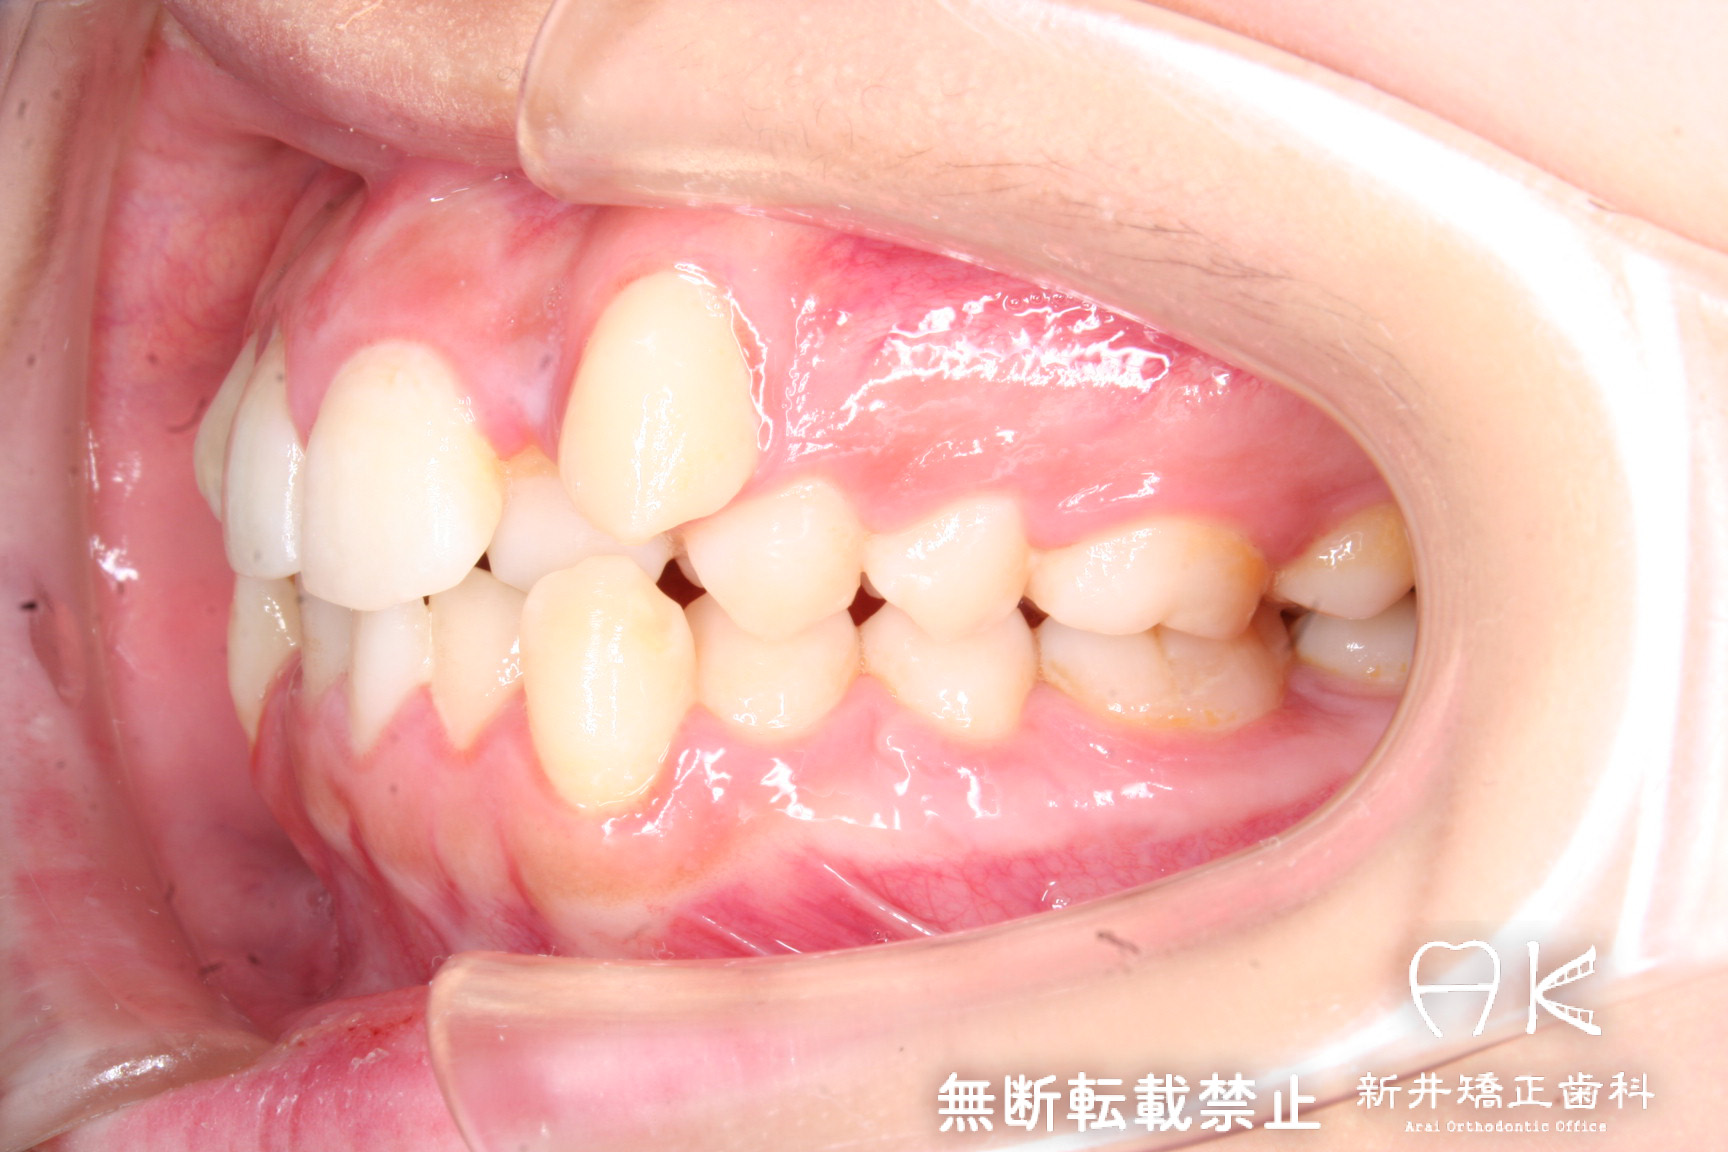

叢生(ガチャ歯・八重歯)と正中のずれの治療

| 症状・診断名 | 叢生 |

| 治療前 | 八重歯や歯のデコボコ、前歯の正中のずれが大きい患者さんでした。 上下顎両側第一小臼歯(前から4番目の歯)を抜歯して治療を行いました。 |